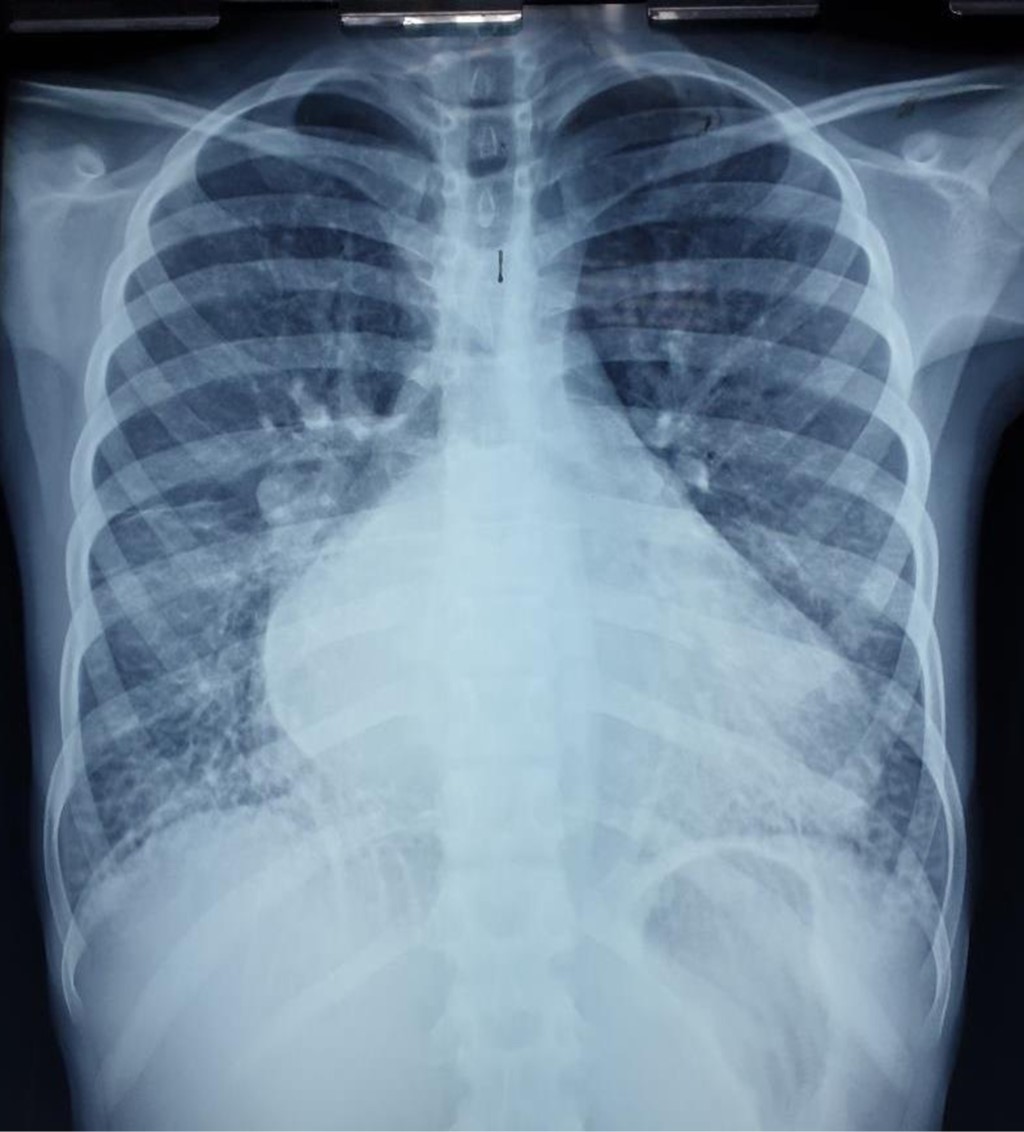

One of the first-degree relatives of the patient had genetic investigations which reported a heterozygous mutation in gene TNNI3, classified as a variant of uncertain significance associated with Dilated cardiomyopathy 2A (OMIM:611880), Dilated cardiomyopathy 1FF (OMIM: 613286), Restrictive cardiomyopathy familial 1 (OMIM: 115210), Hypertrophic cardiomyopathy 7 (OMIM: 613690), all of which have an autosomal dominant inheritance pattern. A diagnosis of cardiomyopathy was suspected due to the clinical presentation and family history. Findings in the initial chest X-ray (Figure 1) revealed cardiomegaly, bilateral atrial enlargement, and pulmonary congestion, and those on the ECG (Figure 2) showed a sinus rhythm, bilateral atrial enlargement, and right ventricle strain supported the suspected diagnosis. The echocardiogram (Figure 3) confirmed the bilateral atrial dilation (LA; 34.8 cm2, RA: 34.1 cm2), an E/A ratio greater than 2, and a PSAP of 47 mmHg, and a left atrial volume of 154 cm3. Using the recommendations for chamber quantification by the European Society of Cardiology, those values were classified as severely abnormal as the atrial volume was above 73 mL. Therefore, indicating severe damage to the left atrium. Abdominal ultrasound confirmed hepatomegaly with dilation of suprahepatic veins. PCR SARS-CoV-2 was negative.

The patient's X-rays, combined with clinical findings, confirmed a global cardiac illness. The electrocardiogram revealed the presence of atrial hypertrophy, which led to echocardiography to determine atrial involvement and measure how much this impacted cardiac function. The echocardiogram reported an atrial diameter of 45.5 mm and an area of 47.7 cm2. According to the European Society of Cardiology,15 the patient had a severe compromise of both her left and right atria. Even though the FEV was not affected, the E/A ratio showed a restrictive filling pattern due to the atrial compromise. In conclusion, a diagnosis of restrictive cardiomyopathy was an adequate diagnosis according to both clinical and echocardiographic data.

Figure 1